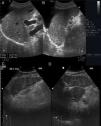

Hemangioma cavernosoTumor benigno hepático más frecuente, con mayor prevalencia en población adulta femenina. El aspecto ecográfico típico10 es reflejo de su histología, mostrándose como una lesión de pequeño tamaño (inferior a 30mm), hiperecoica, bien delimitada, homogénea, con refuerzo acústico posterior y sin captación en el estudio Doppler (fig. 2A). Estas características requieren seguimiento en los siguientes 3-6meses para confirmar la estabilidad de la lesión. En cambio, el aspecto ecográfico atípico (mayor tamaño, heteroecoico con zona central hipoecoica y límites irregulares o mal definidos) requiere de otras técnicas, entre las que encontramos la ecografía con contraste de microburbujas (fig. 2B)11.

Una masa de pequeño tamaño (5cm), bien delimitada, hipoecoica y con un halo fino de menor ecogenicidad (pseudocápsula) (fig. 2C).

Patrón en ojo de toro o en diana. Presenta una zona hipoecoica periférica. Se suele identificar con carcinoma broncógeno (fig. 2D).